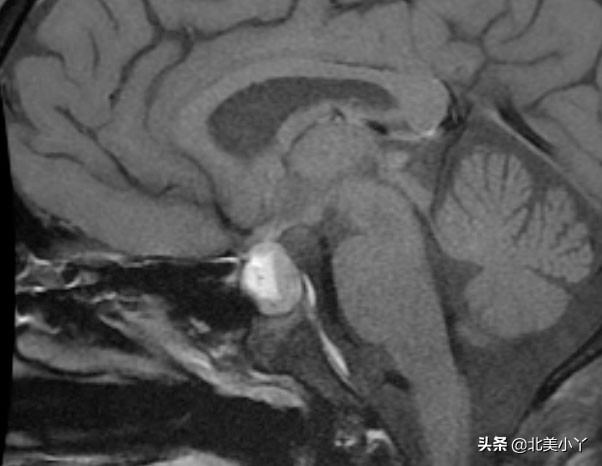

哪些医学方法可以判断得了”蝶鞍邂逅瘤“?

- 神经影像学检查,包括脑CT、垂体加强MRI。

- 神经影像学检查可以帮助诊断疑似的邂逅瘤,但是不能确诊邂逅瘤,确诊只能通过病理组织学分析。